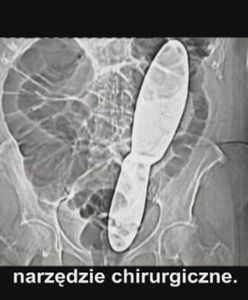

Rażące niechlujstwo lekarzy prawie ją zabiło

Zdenka Kopeckova po wyjściu ze szpitala nie była w stanie funkcjonować. Ból był tak silny, że chciała nawet popełnić samobójstwo. W końcu namówiła lekarzy do wykonania prześwietlenia. Okazało się, że w trakcie operacji, z powodu niechlujstwa personelu medycznego w jej ciele pozostawiono mierzące 30 cm narzędzie chirurgiczne. Pacjentka domaga się odszkodowania.